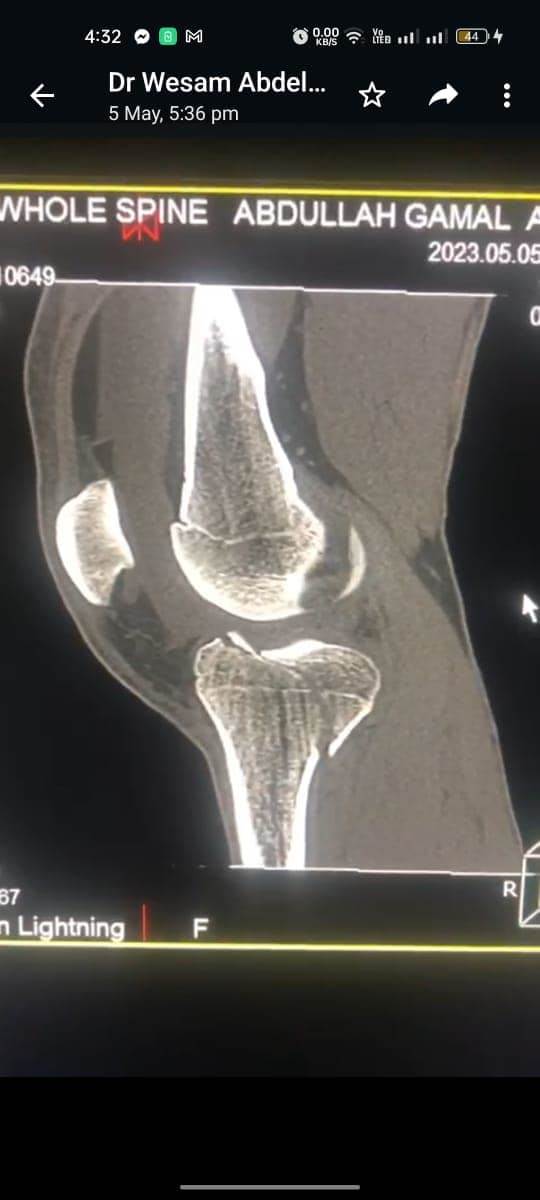

مشيرًا الى أن ذلك النوع من الكسور يكون قريبًا جدًا من الأعصاب والأوعية الدموية الرئيسية للساق والتي توجد خلف مفصل الركبة.. حيث تم الوصول الى الكسر وإعادة بناء سطح المفصل وتثبيته باستخدام شريحة ومسامير وأسلاك معدنية باستخدام جرح ٧ سنتيمترات خلف الركبة واستخدام مسامير جانبية مجوفة بدون فتح لتثبيت الجزء الخارجى من سطح المفصل، وتم الاطمئنان على الأوعية الدموية قبل إفاقة المريض، وبعد تمام الإفاقة.. تم الاطمئنان على الأعصاب والأوعية للمريض.

وأضاف أنه نظرًا لقرب هذا الكسر من سطح المفصل تم عمل أشعة مقطعية بعد الجراحة للتأكد من جودة بناء المفصل وعدم وجود أى بروز للمسامير داخل المفصل، وجارٍ تحضير المريض لعمل رنين مغناطيسى لتحديد الأربطة الداخلية والخارجية للركبة التي ستحتاج لإعادة بناء بالمنظار.